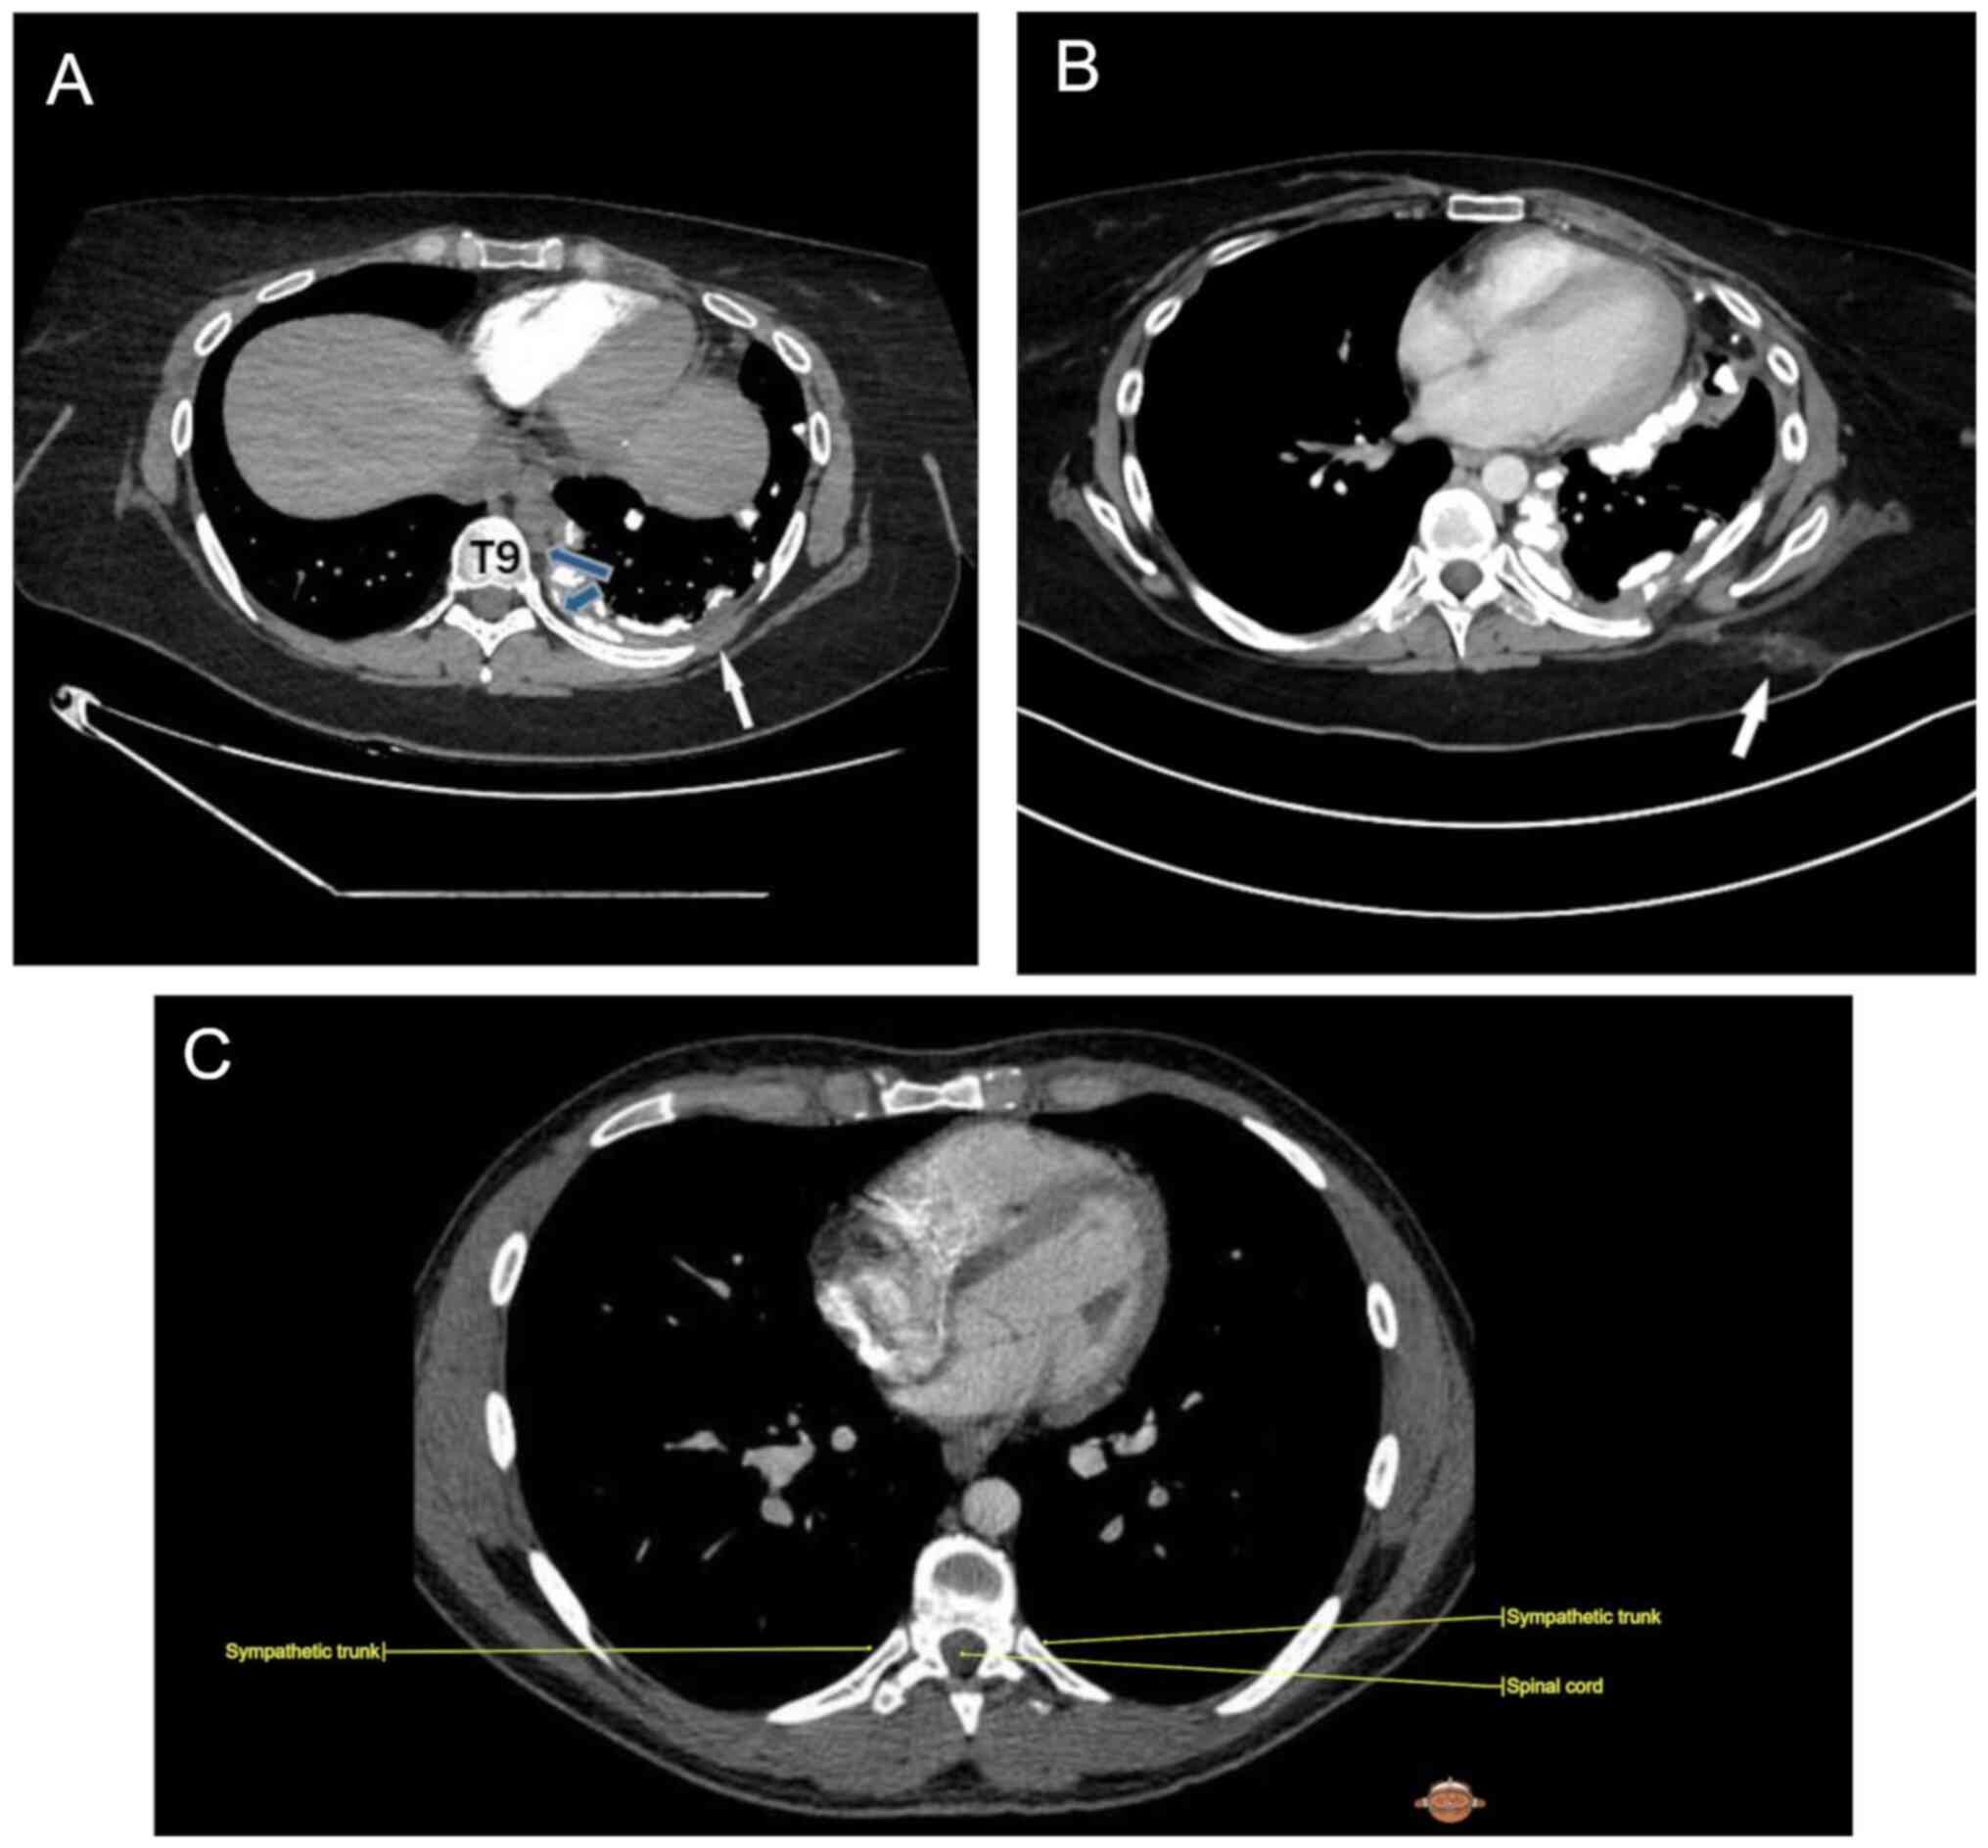

Following emotional distress, on the third day of admission, the female patient presented with right-sided facial flushing and profuse sweating with the left side of the face remaining pale and dry (Fig. 1). The symptoms were resolved spontaneously after 15 min. The physical examination did not reveal any neurological alterations. No ophthalmological abnormalities were observed. Dermatological examination at rest revealed no abnormalities. Routine laboratory studies and carotid artery ultrasonography did not reveal any pathological findings. Pre-operative and post-operative contrast-enhanced CT images illustrated the anatomical region where the iatrogenic injury may have occurred and the diagnosis of iatrogenic HS was considered (Fig. 2A-C) (9). The patient succumbed after 2 days and did not experience any further episodes of Harlequin syndrome prior to their passing.

Figure 2

(A) Pre-operative contrast-enhanced CT image, axial section soft tissue window, demonstrates circumferential and nodular pleural thickening (white arrow) predominantly along the left lateral pleural space including mediastinum pleural surface along with extensive calcifications, representing osteosarcoma pleural metastasis; blue arrows reveal sympathetic chain. (B) Post-operative contrast-enhanced CT image, axial section soft tissue window, demonstrates post-operative changes in the subcutaneous fat of the left hemithorax (arrow) in 8th to 9th intercostal space. (C) Anatomic image of sympathetic track in 8th intercostal place; Courtesy of IMAIOS ©️ ‘Micheau A, Hoa D, e-Anatomy, www.imaios.com, DOI: 10.37019/e-anatomy’. CT, computed tomography.